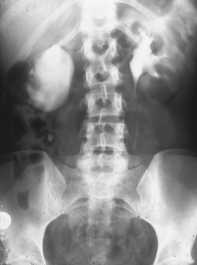

Kasusitik 4

Rechtsseitige Ureterabgangsstenose mit deutlicher Hydronephrose. Behandlung mit Ureterabgangsplastik nach Anderson-Hynes (Abbildung 19).

• Abbildung 19:

1. Rechtsseitige Ureterabgangsstenose mit deutlicher Hydronephrose